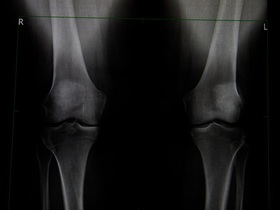

Обладнання для комп'ютерної томографії в МЕДІКОМ

У клініці МЕДІКОМ встановлено сучасний мультиспіральний комп'ютерний томограф Toshiba Aquilion Lightning SP (160 зрізів), який дозволяє обстежити пацієнтів з надлишковою вагою. Апарат КТ складається з кільцеподібного порталу — гентрі, всередині якого розташовані детекторні системи і рентгенівська трубка, і спеціального рухомого стола (діаметр отвору томографа 75 см, максимальний діаметр зони сканування до 50 см, максимально допустима довжина обхвату пацієнта до 200 см).